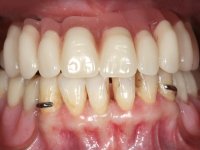

Após análise clínica e imagiológica foi proposto á paciente reabilitar o maxilar superior fazendo a colocação de 4 implantes e posteriormente ser reabilitada com uma Prótese Hibrida.Com a reabilitação proposta, também seria tentada a correção prostodontica da falta de apoio do lábio superior, desde que aprovada esteticamente pela paciente após um “Mock-up” prévio.

Inicialmente foram confecionadas duas novas próteses removíveis. O dente 1.3 foi extraído quando da colocação das próteses. Feito o estudo imagiológico necessário, foram colocados 4 implantes no maxilar superior. Após 3 meses de osteointegração foi feita a impressão para a confeção de ceras de articulação montadas em placa base aparafusadas aos implantes. Estas ceras foram utilizadas na recolha das relações inter-maxilares e na tentativa de proporcionar apoio ao lábio superior. Foi feita a prova de dentes com estes montados em placas base aparafusadas permitindo uma avaliação estética dinâmica muito interessante. Sendo validada esteticamente pela paciente, esta prova deu origem a uma muralha de silicone que orientou laboratorialmente a confeção da infraestrutura metálica. A infraestrutura metálica com os dentes montados em cera foi provada em boca, permitindo simultaneamente verificar a sua adaptação bem como a estética final. O trabalho final foi colocado em boca sendo acompanhado de instruções rigorosas de técnicas de higiene oral bem como da informação da necessidade de consultas de controlo periódicas.